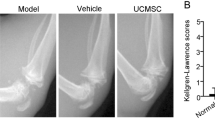

Radiography

Before the animals were euthanized, an X-ray examination was performed on knee joint samples to observe osteophyte formation, joint space, and cartilage damage. All rats were anesthetized with ether at the end of the protocol. The rats were placed in a supine position, and radiographs of the right knee were taken. Two independent investigators blindly evaluated the radiographic grading according to the Kellgren–Lawrence scoring system. The Kellgren and Lawrence system provides a score of severity from 0 to 4 as follows: grade 0, no radiographic features of OA are present; grade 1, doubtful joint space narrowing (JSN) and possible osteophytic lipping; grade 2, definite osteophytes and possible JSN on anteroposterior weight-bearing radiograph; grade 3, multiple osteophytes, definite JSN, sclerosis, possible bony deformity; grade 4, large osteophytes, marked JSN, severe sclerosis, and definite bony deformity [29].

shAHR-hUC-MSCs showed a stronger chondroprotective effect on OA rats

The homeostasis of the articular microenvironment in OA is dysregulated or even disordered. It is unclear whether the cartilage protective efficacy of hUC-MSCs is affected after injection into the joint cavity. Our results suggest that OA SF affects chondrogenesis and proliferation of hUC-MSCs, probably by activating the KYN–AHR axis in vivo. To investigate the role of AHR in the repair of cartilage damage by hUC-MSCs in vivo, a surgically induced OA rat model was established. All OA rat models received different treatments as described in the Methods section. X-rays were used to detect knee joint lesions. The imaging results showed that, compared with the sham group, the wear and tear of the cartilage surface was significantly more in the OA group, and the shNC group also showed mild symptoms of joint wear (Fig. 6A). The cartilage surface was smoother in both the shAHR and sham groups, and the joint space was more obvious than that in the OA and shNC groups (Fig. 6A). The radiographic grading score system suggested that cartilage lesions in the OA and shNC-hUC-MSC groups were significantly higher than those in the shAHR group (Fig. 6A). The gross morphology of the knee cartilage and the OARSI score showed that compared with the shNC group, the shAHR group could significantly attenuate cartilage damage and had a better therapeutic effect on cartilage regeneration (Fig. 6B). Furthermore, safranin-O and fast green staining revealed that both the shNC-hUC-MSC and shAHR-hUC-MSC groups attenuated cartilage lesions and promoted cartilage regeneration, with the shAHR group having more cellularity and fewer superficial layer losses than the shNC group (Fig. 6C). Immunohistochemistry revealed that cartilage matrix collagen II (Fig. 6D) and aggrecan (Fig. 6E) expression levels in the shAHR group were more substantial than those in the shNC group and slightly lower than those in the sham group. These findings show that shAHR-hUC-MSCs significantly reduced cartilage damage in the rat model and provided better cartilage protection than shNC-hUC-MSCs in the rat OA model.

The effect of shAHR-hUC-MSCs on cartilage protection in vivo. A X-ray was used to evaluate the severity of OA in the knee joint before the animals were euthanized and the degree of cartilage lesions and osteophyte formation were assessed by the Kellgren–Lawrence scoring system (n = 5). B Gross morphology of articular cartilage damage of rats from different group, and cartilage destruction was evaluated using the OARSI scoring system (n = 5). C Safranin O-fast green staining for histopathologically observing the articular cartilage damage of rats from different group, and Mankin’s score was used to evaluate the degree of cartilage destruction (scale bar = 200 μm, scale bar = 100 μm) (n = 5). D, E Immunohistochemical staining was used for assessing the expression of Collagen II and Aggrecan, and their quantitative analysis (scale bar = 200 μm, scale bar = 100 μm) (n = 5). F, G Immunohistochemical staining was used for assessing the expression of IDO1 and TDO2 in the synovial tissues of healthy (post-trauma) people, OA, and RA patients (scale bar = 200 μm, scale bar = 100 μm) (n = 3). H, I Immunohistochemical staining was used for assessing the expression of IDO1 and TDO2 in the synovial tissues of normal, OA, and RA rats (scale bar = 200 μm, scale bar = 100 μm) (n = 3). Data were expressed as means ± SEM. *P < 0.05, **P < 0.01